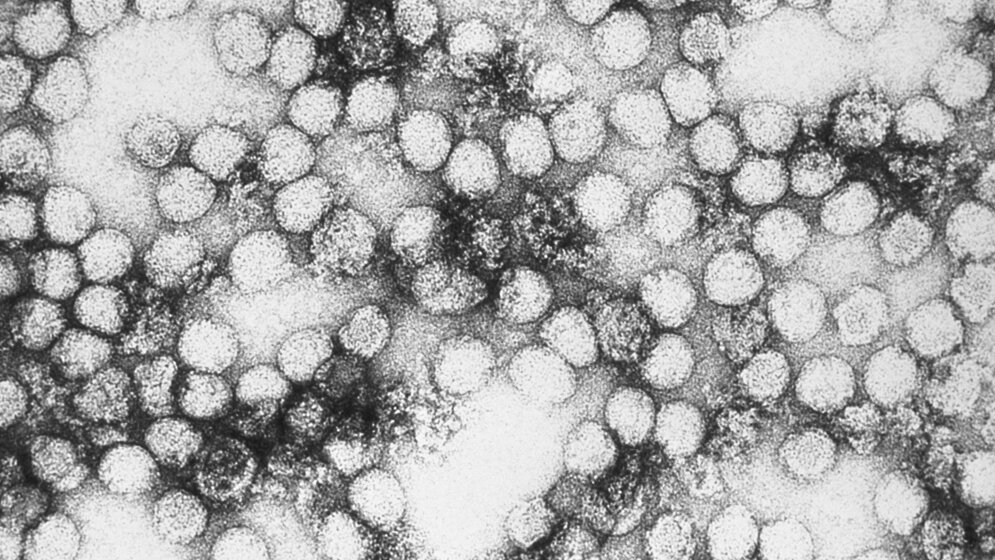

Laut Wellcome Trust werden die COVID-19-Kosten etwa 11 Billionen USD bis Ende 2021 betragen. Das Nicht-vorbereitet-sein kostet deutlich mehr als die Eindämmung von Infektionskrankheiten. Viele Ausbrüche schaffen es noch nicht einmal in die Nachrichtensendungen. Anbei finden Sie die „Top 10“ der vergangenen Jahre. Quelle: WHO/IHM data as of 12 January 2018